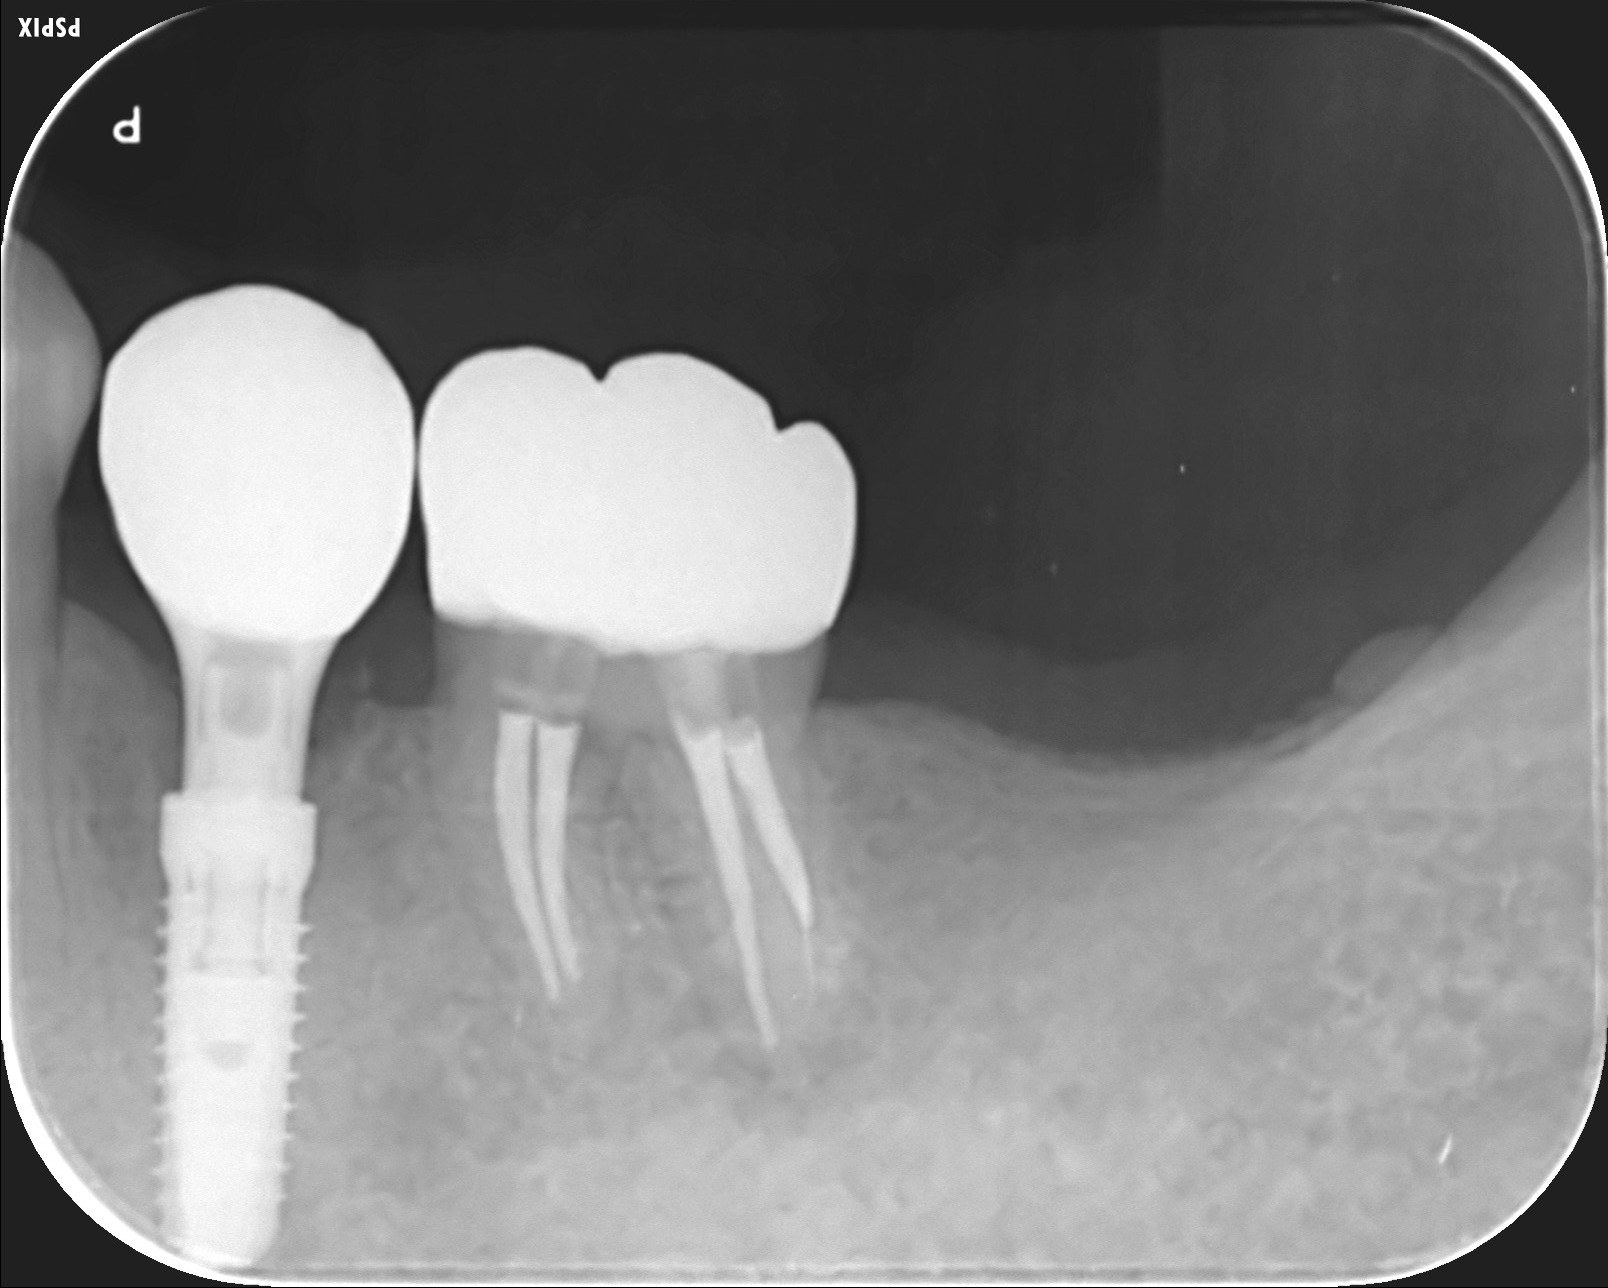

X線写真

骨の状態も安定しています。